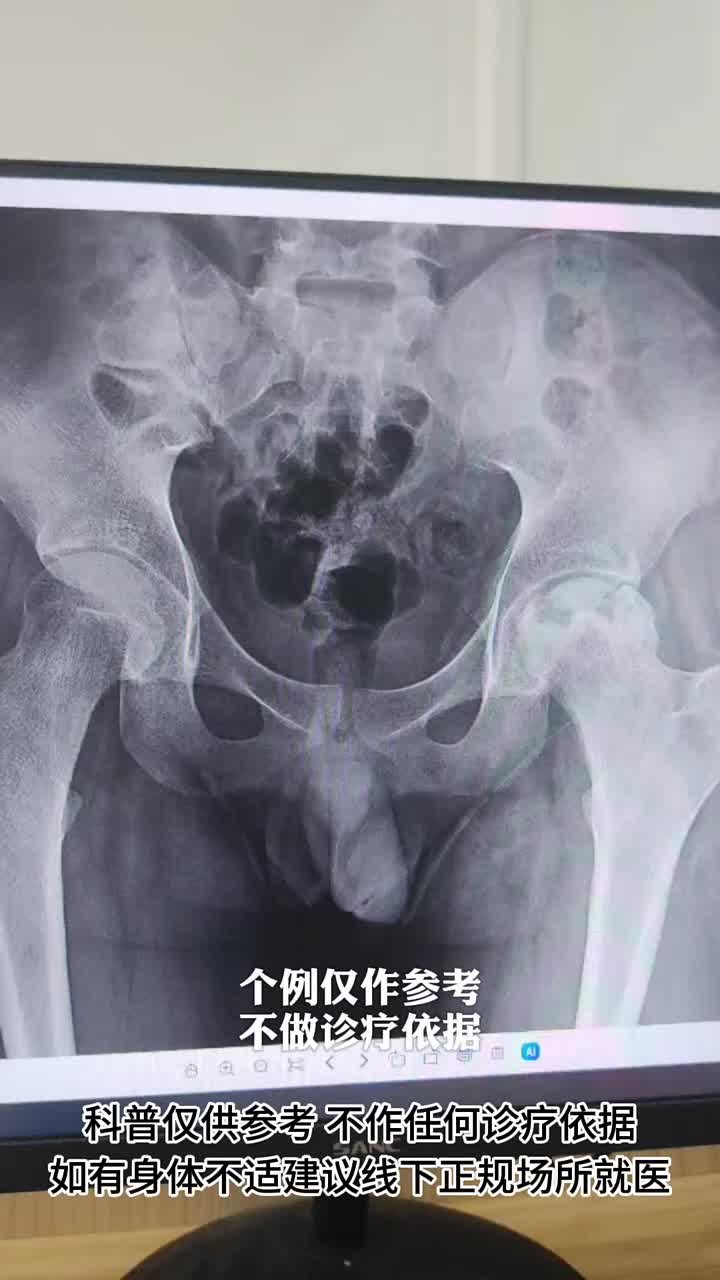

双侧股骨头坏死,影像左侧重,症状右侧重,先做哪一侧?

股骨头坏死,为什么患者需按分期展开治疗?